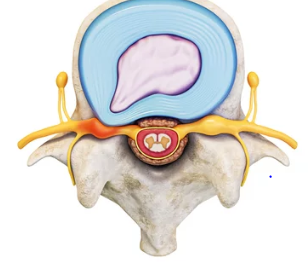

허리 디스크, 또는 추간판 탈출증은 척추의 디스크가 제자리에서 벗어나 주변 신경을 압박하는 상태를 말합니다. 이로 인해 통증, 저림, 감각 이상 등 다양한 증상이 나타날 수 있습니다. 허리 디스크의 가장 흔한 증상은 허리 통증이며, 이 통증은 다리로 방사될 수도 있습니다. 또한, 디스크가 신경을 압박하면 해당 신경이 지배하는 영역에 감각 이상이나 근력 약화가 발생할 수 있습니다.

허리 디스크의 증상은 사람마다 다르게 나타나며, 일부 사람들은 아무런 증상이 없을 수도 있습니다. 하지만 일반적으로 다음과 같은 증상들이 관찰됩니다:

1. 허리 통증: 특히 오래 서 있거나 앉아 있을 때, 무거운 물건을 들었을 때 통증이 심해질 수 있습니다.

2. 다리로의 방사통: 허리에서 시작된 통증이 엉덩이, 대퇴부, 종아리, 발까지 이어질 수 있습니다.

3. 감각 이상: 디스크에 의해 압박된 신경으로 인해 저림, 찌릿함, 또는 마비감을 느낄 수 있습니다.

4. 근력 약화: 신경 압박이 오래 지속되면 해당 신경이 지배하는 근육의 힘이 약해질 수 있습니다.